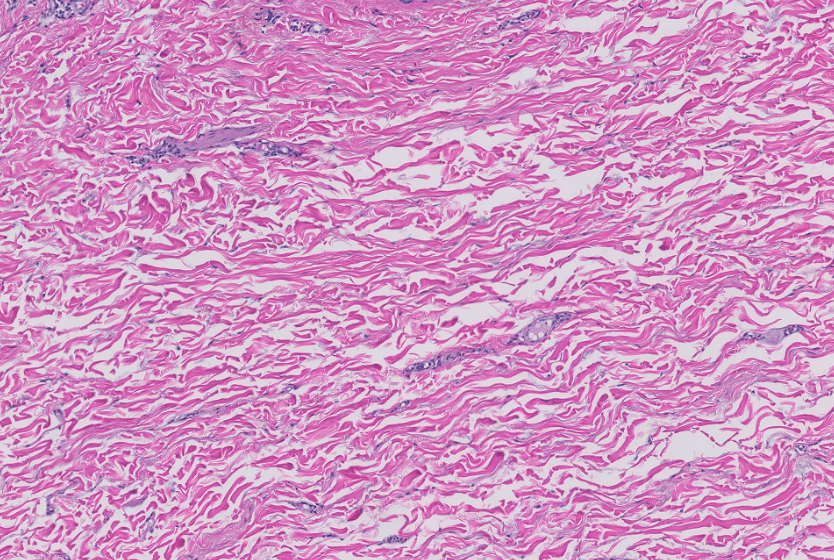

There was no modification in operative technique to the patients included in this study compared with the excluded patients undergoing breast reduction mammaplasty at this institution. Postoperative course was dictated by the normal routine for any postoperative patient having undergone reduction mammaplasty. There were no changes in the clinical decision-making algorithm. All patient information was de-identified, encrypted, and stored in a secure, password-protected database using REDCap software (Vanderbilt University). Figures 1 and 2 demonstrate pathologic slides showing high- and low-density SDPs, respectively.

If the tissue was satisfactory, an additional glass slide was prepared and subjected to CD-34 immunohistochemical staining to highlight vascular endothelial cells. Each section was evaluated using a 10× high-powered field (hpf). The SDP density was evaluated at the dermal-epidermal junction and is presented as the number of vascular structures that show positivity for the CD-34 stain seen in one 10× hpf. Each tissue sample that was satisfactory and stained with CD-34 was assessed at 10× over 10 fields across the tissue sample to provide 20 samples per patient that were used to calculate an average density that was considered a representative average density for that particular patient.